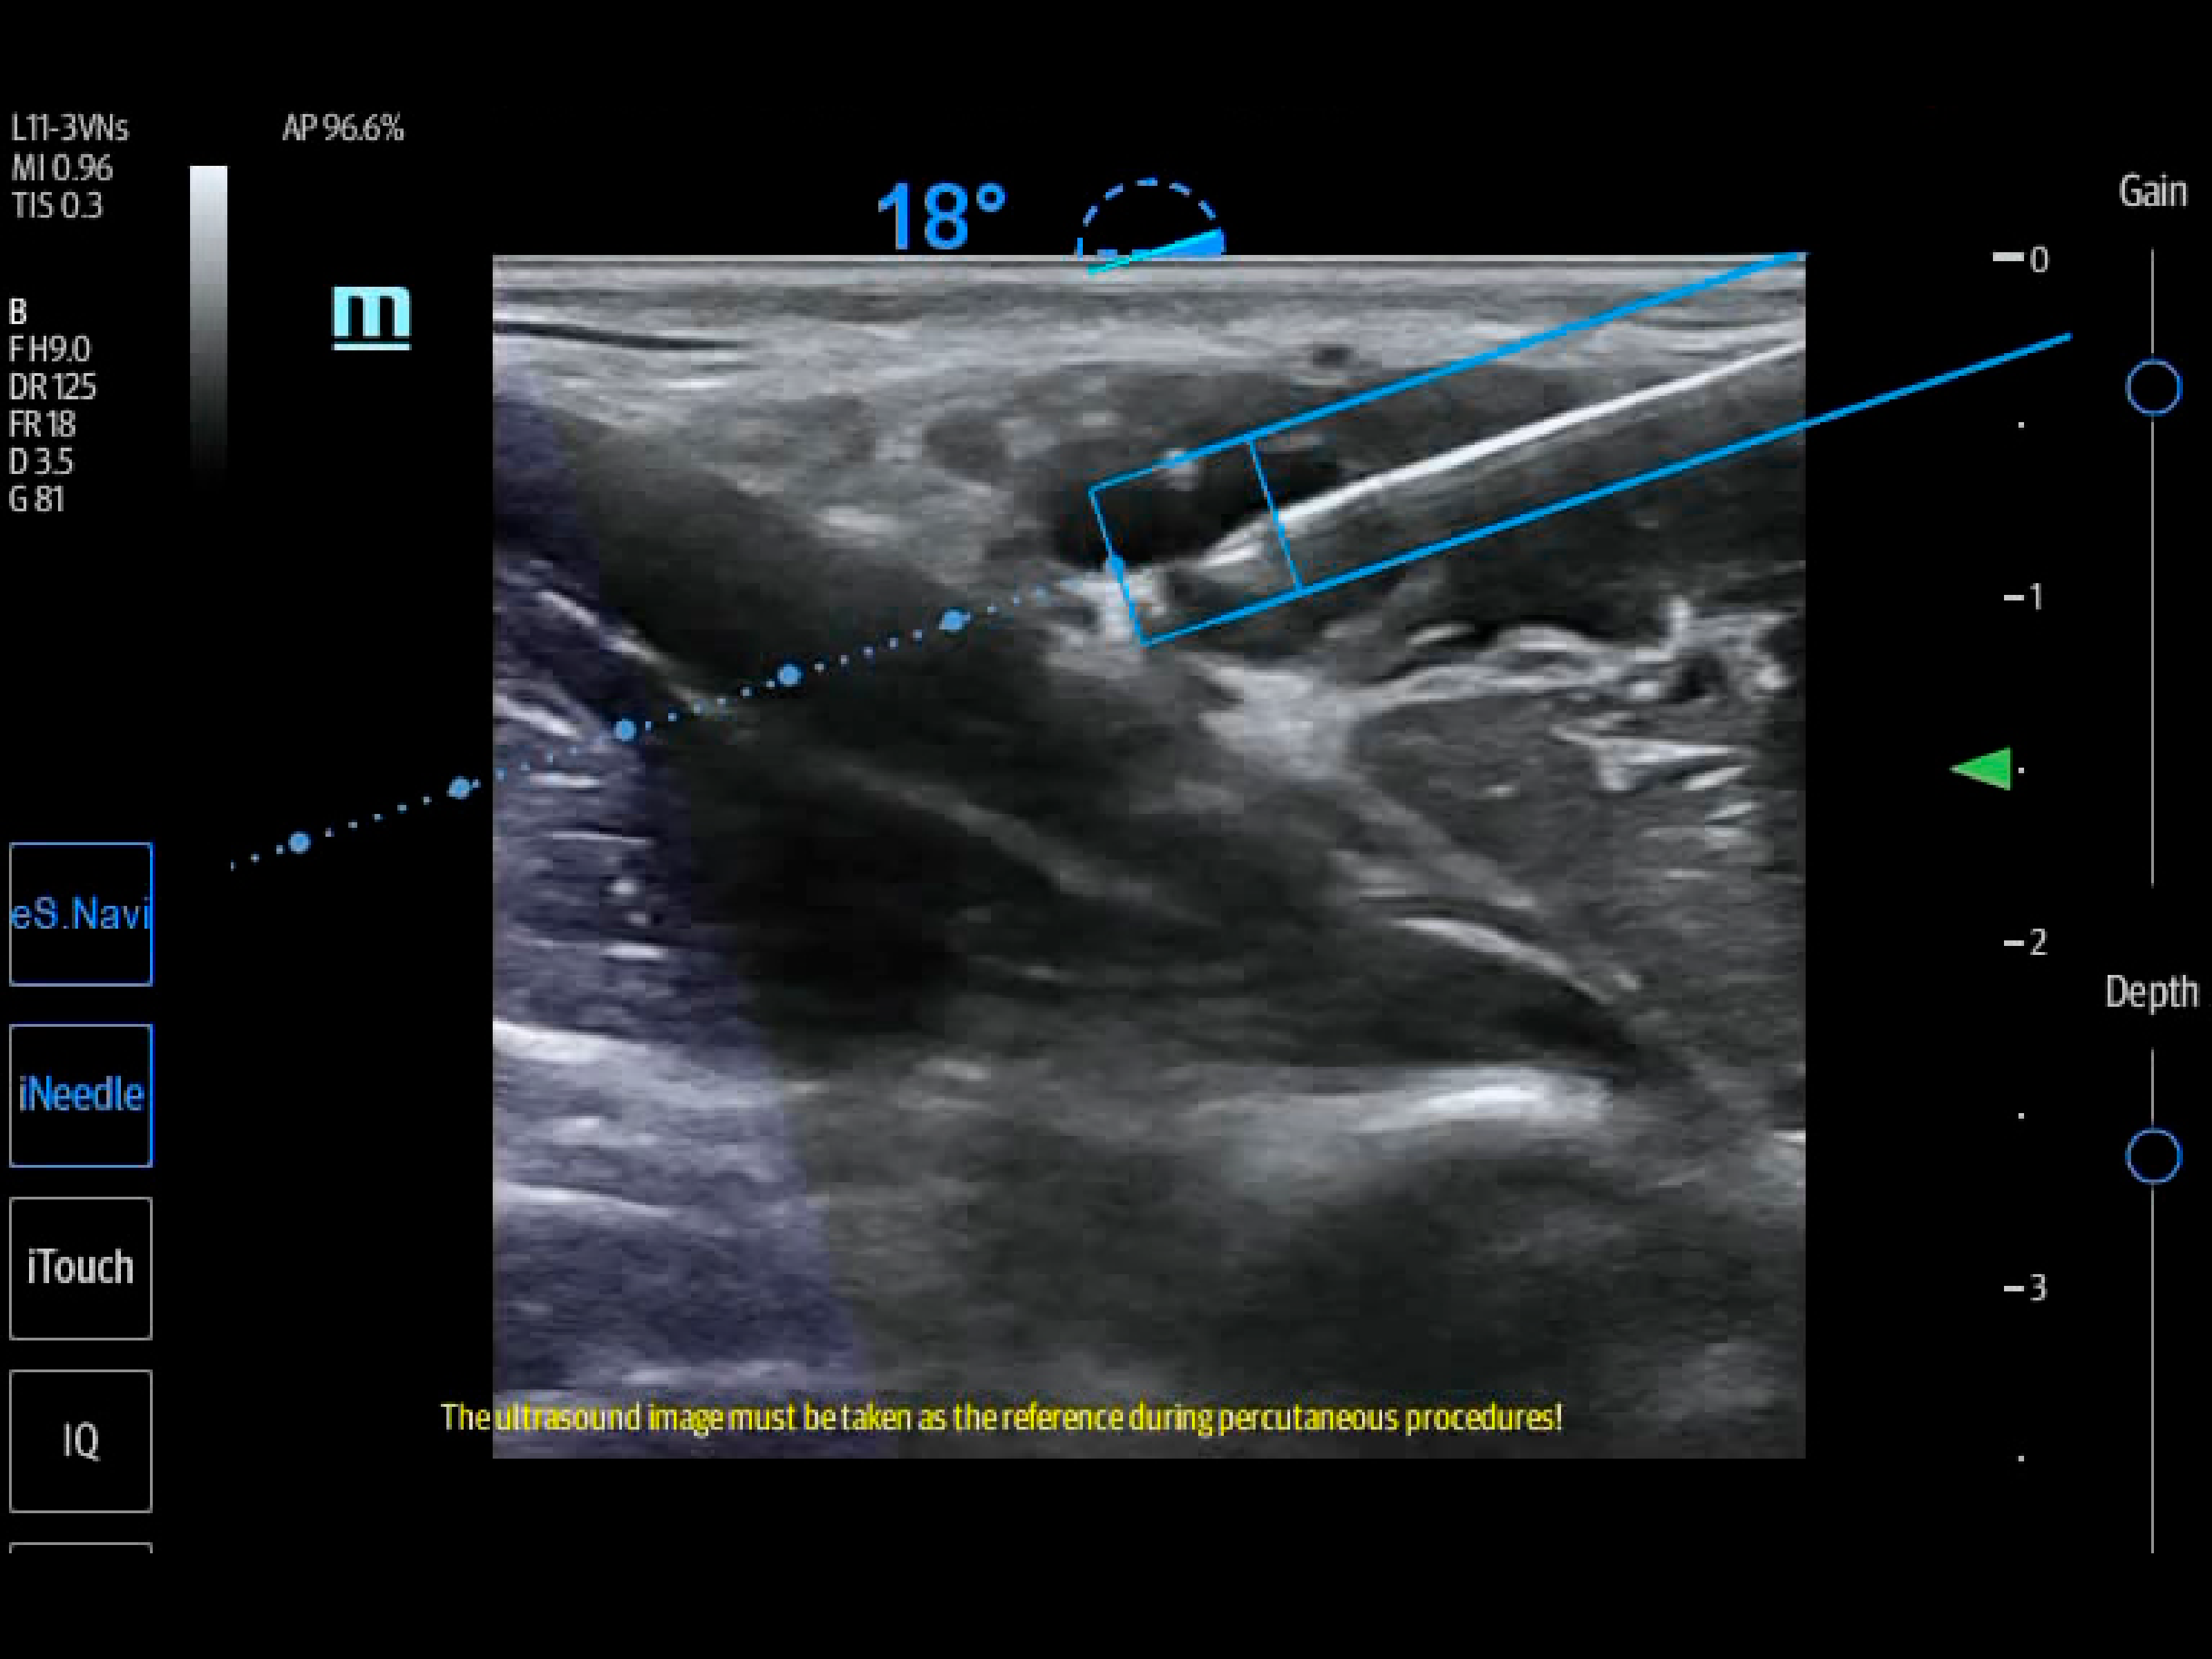

The TE7 Ultrasound System Crystal Series 2.0 is the system of choice from routine point-of-care exams to extreme situations when every second counts. With best-in-class image quality, a sleek form factor, and breakthrough needle visualization advancements, the TE7 System is designed to provide superior performance for rapid, confident exams and procedures in the fast paced, point of care environment.

The TE7 System incorporates an intuitive touchscreen and focused point-of-care protocols designed to standardize and reduce exam times. The System’s second generation iVocal voice recognition technology and new programmable-button transducer technology allows for a hands-free scanning experience, ideal for sterile environments.